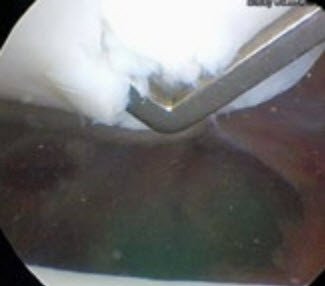

Die Belastung des Gelenkknorpels ist im Bereich des Kniescheibengelenks die grösste im gesamten Körper. Dementsprechend ist der Knorpel im Bereich der Kniescheibe (Patella) besonders dick, in Einzelfällen bis zu acht Millimeter. Eine effektive Rekonstruktion des patellaren Knorpels stellt aus diesem Grund eine besondere Herausforderung an den behandelnden Arzt.1 Gerade an dieser Lokalisation spielt die Qualität des Knorpels eine besonders grosse Rolle, um der biomechanischen Belastung auf lange Zeit standzuhalten. Es existieren verschiedene Techniken, defekten Knorpel zu rekonstruieren. Darunter bringt die autologe Knorpelzelltransplantation (ACT) wahrscheinlich die höchste Regeneratqualität hervor. Diese Technik wird nun schon seit fast 30 Jahren weltweit eingesetzt, nachdem sie in den späten 1980er-Jahren in Schweden etabliert worden ist.2 In der Literatur sind sehr zufriedenstellende Langzeitresultate vorzufinden.3, 4 Zur Realisierung erfolgt eine initiale Arthroskopie des Kniegelenks zur Erhebung des Binnenstatus und eine Evaluation des vorliegenden Knorpelschadens.

In diesem Fall bestätigte sich der Verdachtsbefund und es zeigte sich an der Patellagelenkfläche ein ausgedehnter und vollschichtiger Knorpelschaden (Abb. 2). In der gleichen Arthroskopie wurden Knorpelzellproben aus einer nicht belasteten Stelle des Gelenks entnommen (Abb. 3). Solche Proben werden jeweils zu einer Tissue-Engineering-Firma gesendet. Dort werden die Knorpelzellen in eine Zellkultur transferiert, um deren Zahl zu erhöhen.